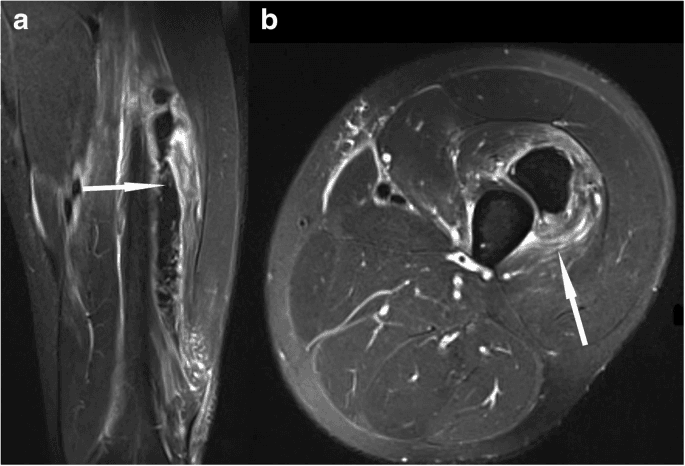

As lesões de grau II são mais sérias e caracterizadas por uma ruptura parcial das fibras musculares. Os sintomas incluem dor intensa, inchaço e dificuldade em mover o músculo lesionado. Nesse caso, é fundamental interromper a atividade física imediatamente para evitar uma agravamento da lesão. O tempo de recuperação pode variar de alguns dias a semanas, dependendo da gravidade.

Por fim, as lesões de grau III são as mais severas, resultando em uma ruptura completa do músculo. Os sintomas incluem dor intensa, inchaço significativo, hematomas e, em alguns casos, a incapacidade de movimentar a parte afetada. Esse tipo de lesão geralmente requer intervenção médica e pode necessitar de cirurgia, além de um longo período de reabilitação.